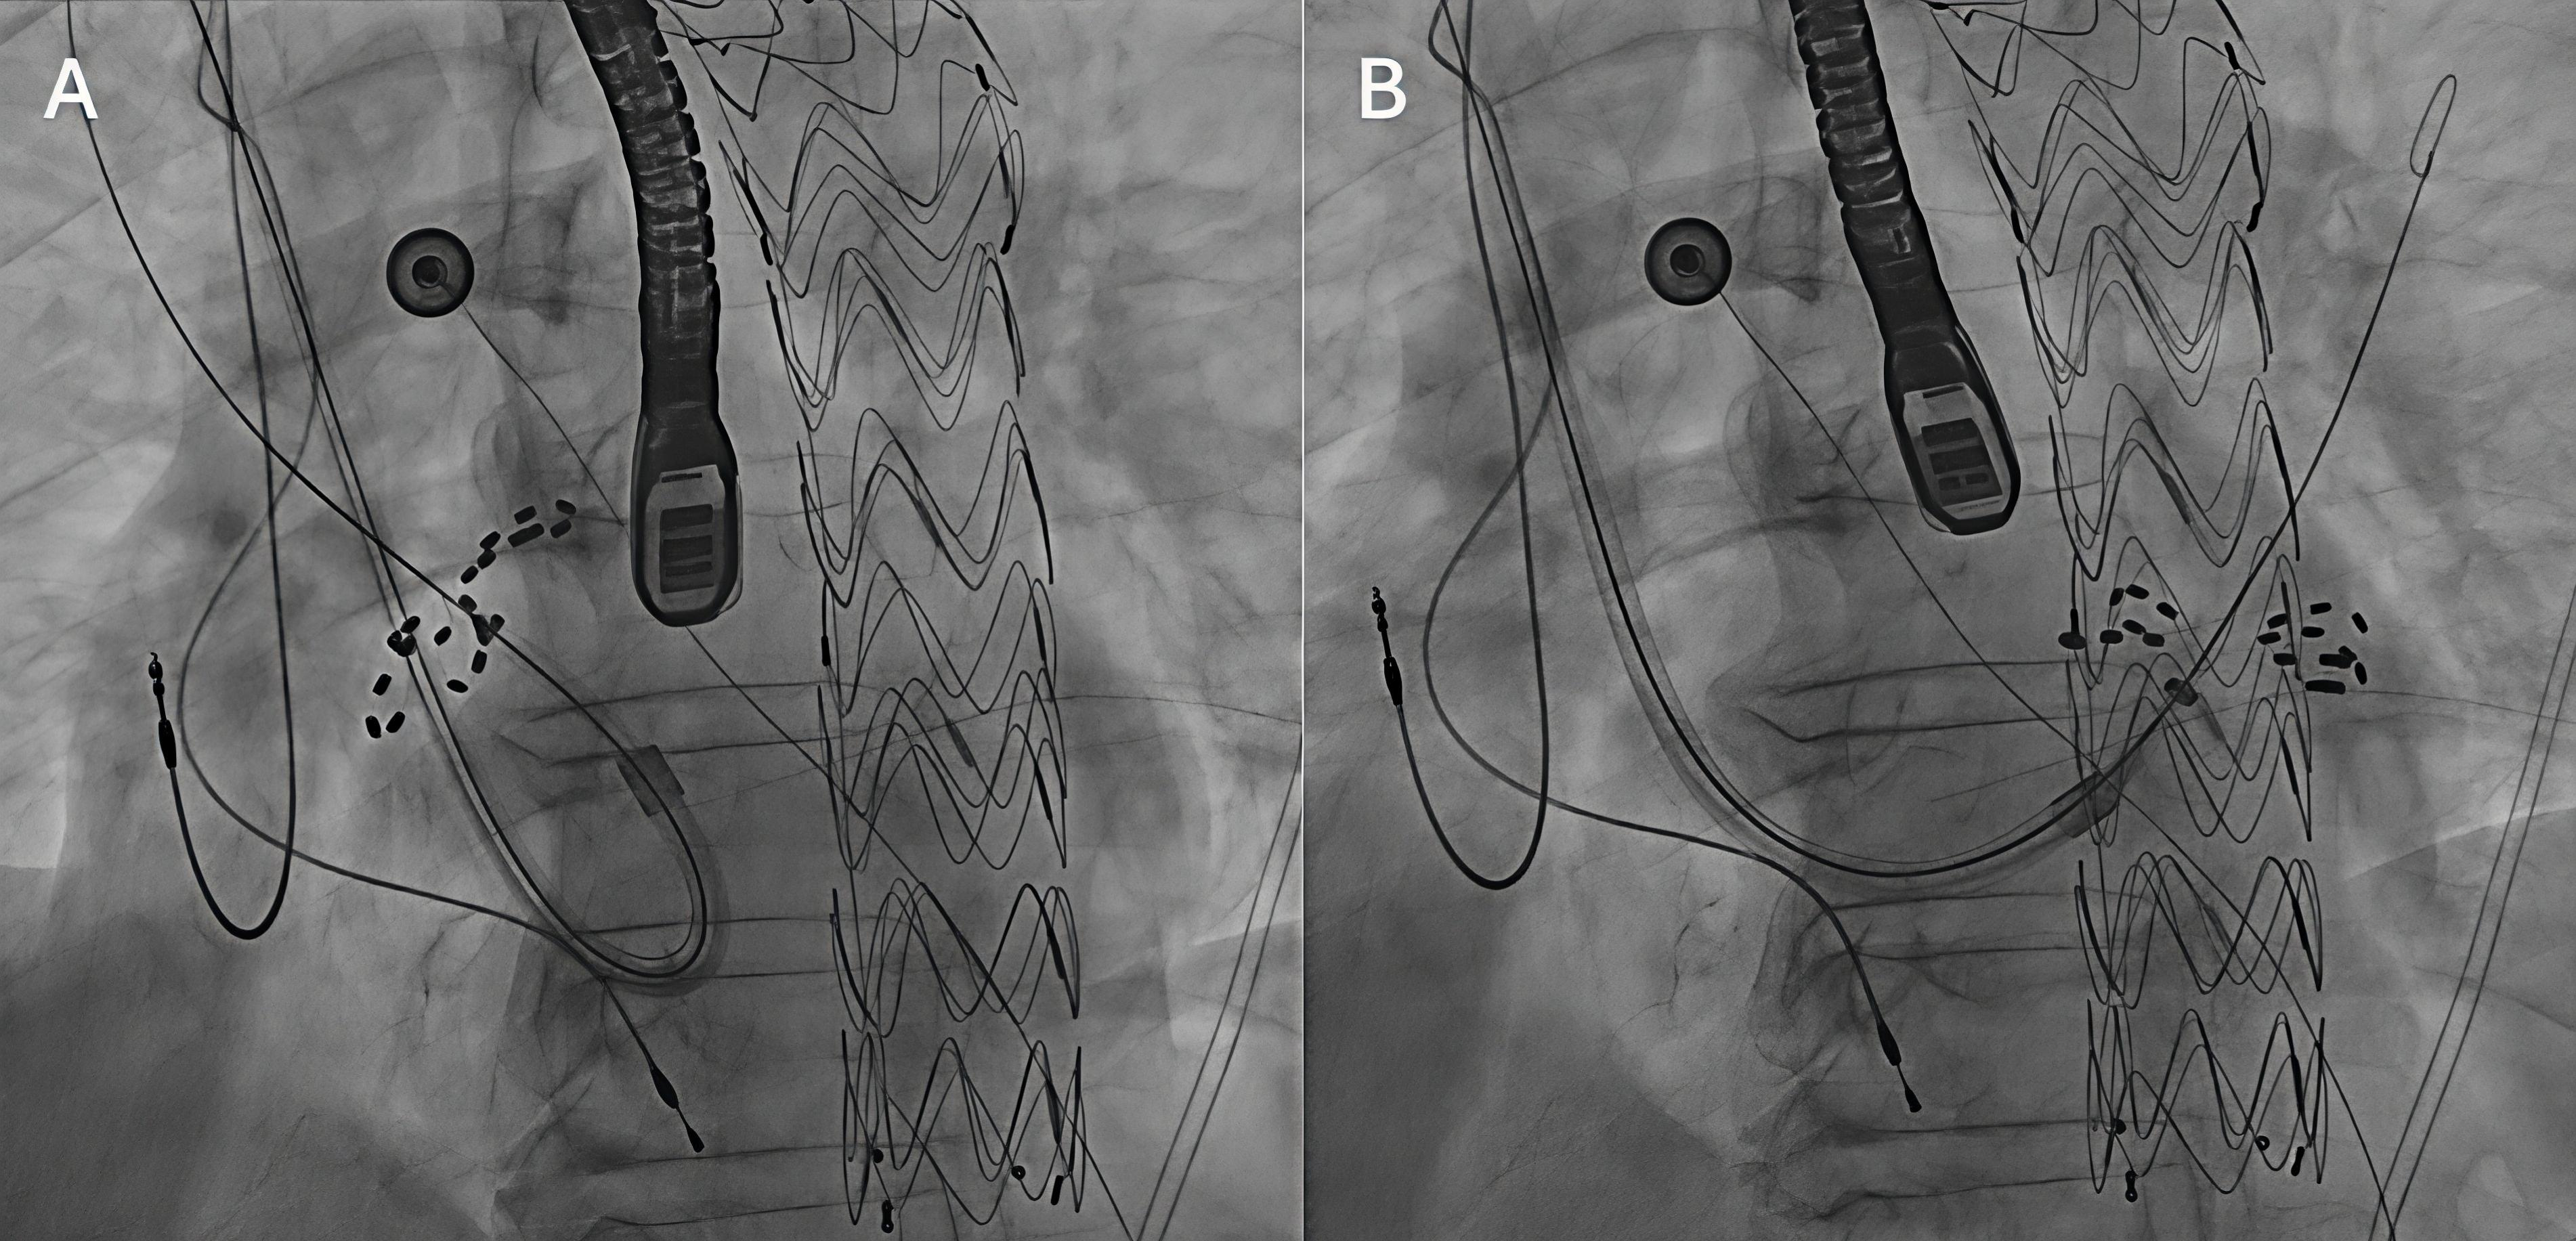

An initial femoral approach was aborted when an inferior vena cava (IVC) filter was encountered. Attempts to pass wires and sheaths through the filter resulted in appreciable filter movement under fluoroscopy, raising concern for dislodgment or vascular injury. The procedure was terminated without complication, and ablation was rescheduled using an alternative access strategy (Figure 1, Video).

Pulmonary vein isolation was subsequently performed using pulsed field ablation (PFA) via the right internal jugular (RIJ) vein. RIJ access was obtained under ultrasound guidance. Transesophageal echocardiography excluded intracardiac thrombus and guided transseptal puncture using an Agilis steerable sheath (Abbott), ProTrack pigtail wire (Baylis), and a Bovie device (Medtronic Covidien). Because the superior route requires approaching the fossa ovalis from above, operators must work through a steeper and less favorable transseptal angle, and catheter manipulation can be more challenging. Awareness of reduced catheter stability, as well as the altered torque response and fluoroscopic orientation inherent to a superior-only approach, was important for navigation of the left atrium. Heparin was administered to maintain an activated clotting time of 300 to 350 seconds. The sheath was then exchanged for the FARAPULSE system (Boston Scientific), and all 4 pulmonary veins were successfully isolated with demonstration of exit block (Figure 2). PFA was selected for its tissue-selective, non-thermal mechanism that reduces collateral injury risk. Post-procedure electrocardiography showed atrial pacing with left axis deviation and left bundle branch block.